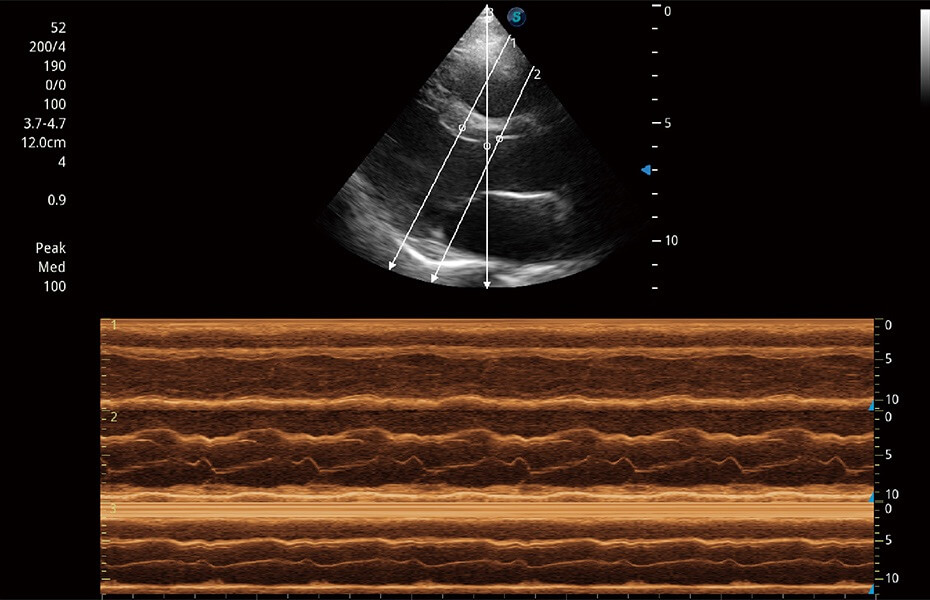

ProPet 60 作為一款高端臺(tái)式動(dòng)物超聲設(shè)備,為動(dòng)物醫(yī)生的日常診斷提供了一系列貼合動(dòng)物臨床需求、解決臨床實(shí)際問題的高級成像功能。憑借全系列高清探頭,滿足醫(yī)生對腹部、心臟、生殖、淺表、肌骨等成像的所有需求,切實(shí)幫助您提升檢查效率,提高診斷信心。